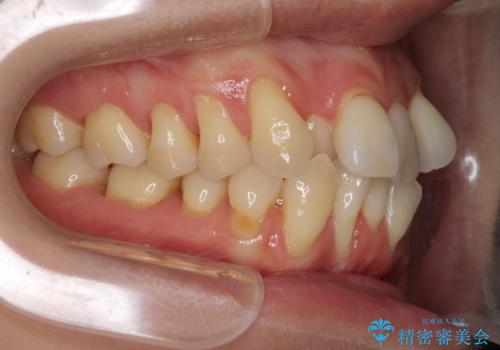

- 上下前歯のでこぼこを気にされ、矯正治療を希望された患者様です。

費用を抑えるため、メタルブラケットを採用し、抜歯矯正を行うこととしました。

通常であれば、上下顎左右小臼歯各1歯の合計4本を抜歯しますが、歯肉退縮の著しい下顎前歯を抜歯して欲しいという患者様の強い希望により、上顎のみ左右小臼歯2歯を、下顎は前歯を1歯を抜歯することとしました。

抜歯する歯を変更したため奥歯の咬合はアンバランスとなりましたが、前歯は綺麗に整い、歯肉退縮も回避できました。